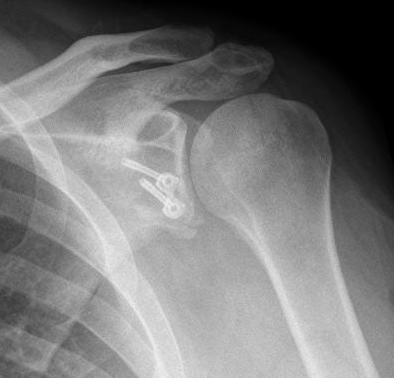

Glenoid fractures occur the margins of the shoulder joint on the scapula side and are largely due to the trauma of a shoulder dislocation. Surgery may be needed but depends more on the features of the dislocation than the fracture itself.

Other parts of the scapula can be fractured such as the scapula spine, the coracoid process or the acromion. Each is managed individually most without surgery.

The proximal humerus may fracture into multiple fragments or individual single pieces of bone associated with the attachment of the rotator cuff. Each of these fractures require careful assessment and if displaced surgical management as they are the attachment of the rotator cuff.